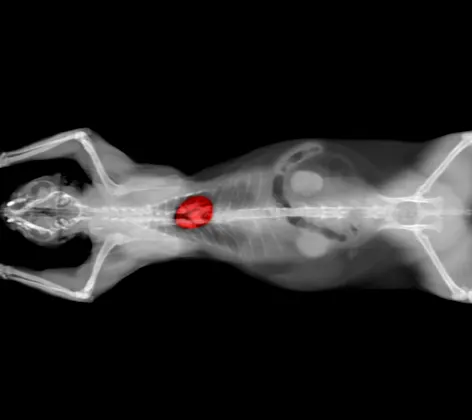

Computed Tomography / CT Scan

Computed Tomography is a way of examining bodily organs by scanning them with X rays and using a computer to construct a series of cross-sectional images that run along a single plane.

Magnetic Resonance Imaging (MRI)

Magnetic Resonance Imaging provides good contrast between different tissues of the body.